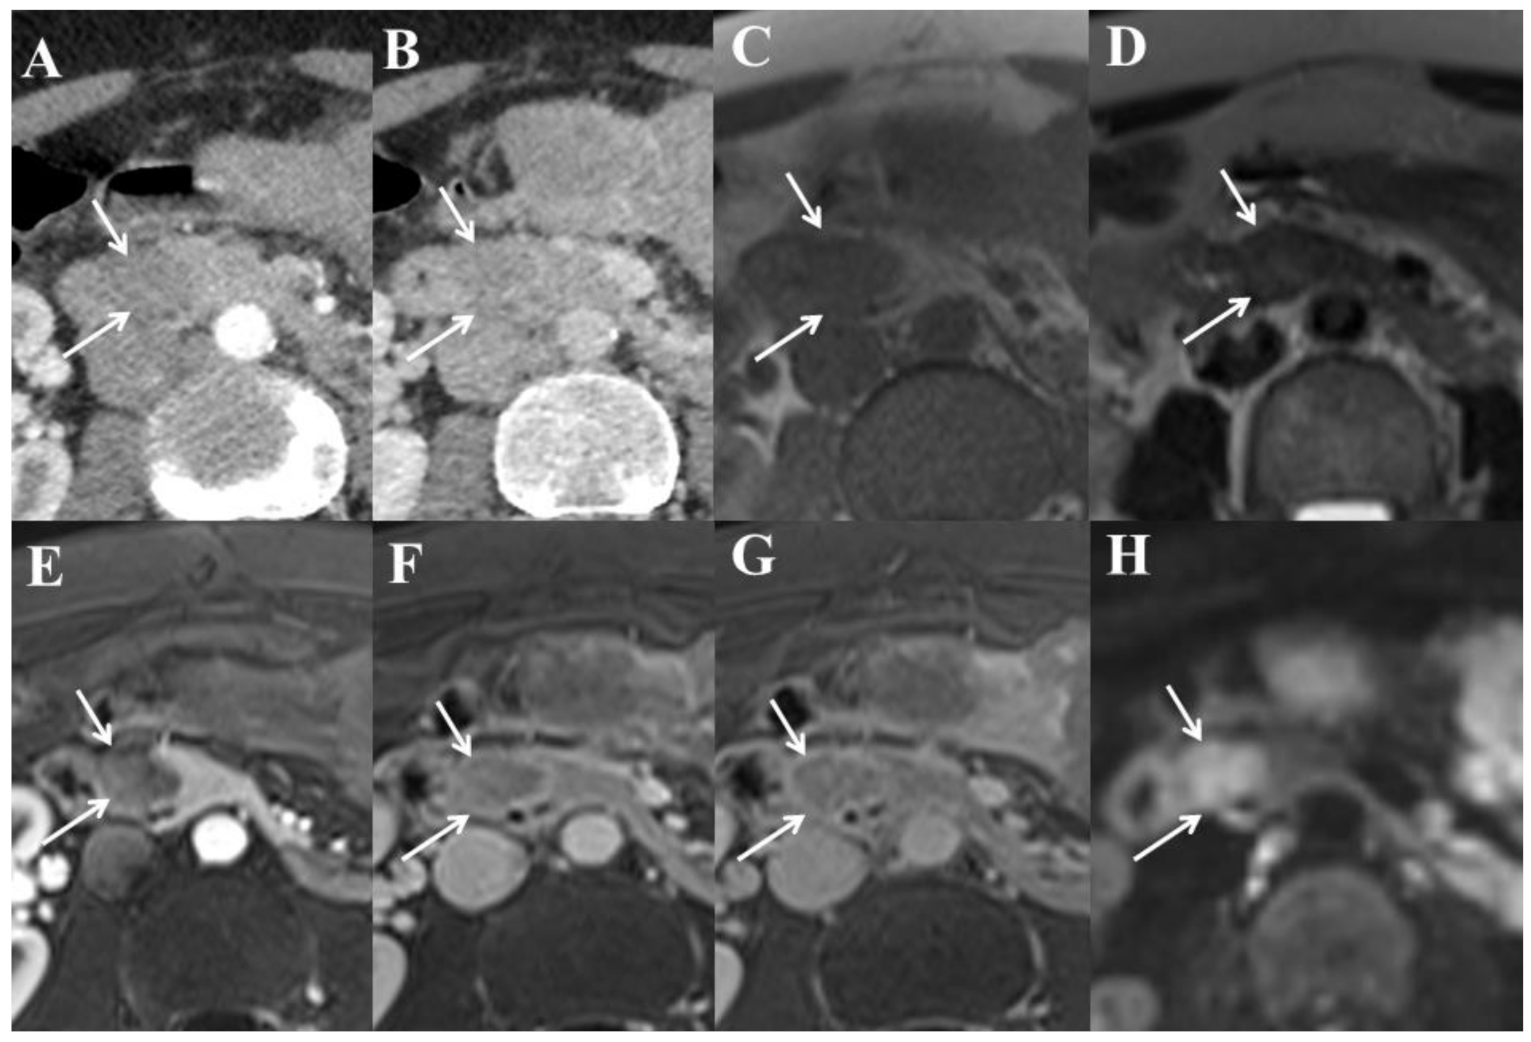

3.2. Morphological Imaging and Radiomics

- Canellas, R.; Burk, K.S.; Parakh, A.; Sahani, D.V. Prediction of pancreatic neuroendocrine tumor grade based on CT features and texture analysis. AJR Am. J. Roentgenol. 2018, 210, 341–346. [Google Scholar] [CrossRef] [PubMed]

- Choi, T.W.; Kim, J.H.; Yu, M.H.; Park, S.J.; Han, J.K. Pancreatic neuroendocrine tumor: Prediction of the tumor grade using CT findings and computerized texture analysis. Acta Radiol. 2018, 59, 383–392. [Google Scholar] [CrossRef] [PubMed]

- Guo, C.; Zhuge, X.; Wang, Z.; Wang, Q.; Sun, K.; Feng, Z.; Chen, X. Textural analysis on contrast-enhanced CT in pancreatic neuroendocrine neoplasms: Association with WHO grade. Abdom. Radiol. 2019, 44, 576–585. [Google Scholar] [CrossRef] [PubMed]

- Azoulay, A.; Cros, J.; Vullierme, M.-P.; de Mestier, L.; Couvelard, A.; Hentic, O.; Ruszniewski, P.; Sauvanet, A.; Vilgrain, V.; Ronot, M. Morphological imaging and CT histogram analysis to differentiate pancreatic neuroendocrine tumor grade 3 from neuroendocrine carcinoma. Diagn. Interv. Imaging 2020, 101, 821–830. [Google Scholar] [CrossRef]

- Bartoli, M.; Barat, M.; Dohan, A.; Gaujoux, S.; Coriat, R.; Hoeffel, C.; Cassinotto, C.; Chassagnon, G.; Soyer, P. CT and MRI of pancreatic tumors: An update in the era of radiomics. Jpn. J. Radiol. 2020, 38, 1111–1124. [Google Scholar] [CrossRef]